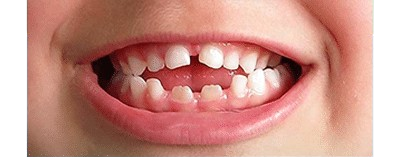

Hay una abertura entre los dientes superiores e inferiores

Posicionamiento inadecuado de los dientes.